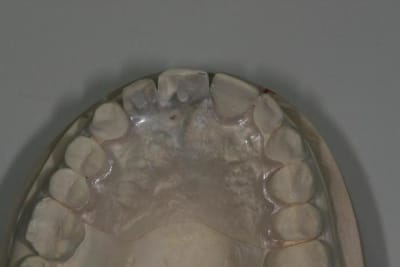

Bon ben j'ai implanté avant d'avoir refait la 21. Du coup j'ai mésialé la pose de 11 pour compenser la distalisation de 21.

Au final je n'ai pas fait de greffe osseuse... et j'ai réalisé une technique de rouleau sur 11-12 mais je reste un peu court à mon goût.

J'ai mis en place des transitoires sur 11-12-21 pour temporiser 3 mois pour voir la maturation des tissus mous.

Je mets quelques photos de la patiente au cab et du prothèsiste d'Epinal.

Les provisoires sont solidaires ? ( bravo pour le parallélisme)

Le zénith de la 21 doit être un peu plus distal pour que le résultat soit plus sympa